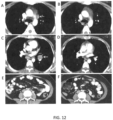

• Computed tomography (CT) scans of the chest and pelvis of Patient 4 were carried out before treatment and nine months after treatment.

• CT Computed tomography

• Figures 12A-F the cancerous lesion in the paraaortic lymph node had shrunk by 100% nine months after treatment.

• Figures 12C-D the cancerous lesion in the left lung hilar lymph node had also shrunk by 100% nine months after treatment.

• Figures 12E-F the cancerous lesion in the common iliac lymph node had also shrunk by 100% nine months after treatment.